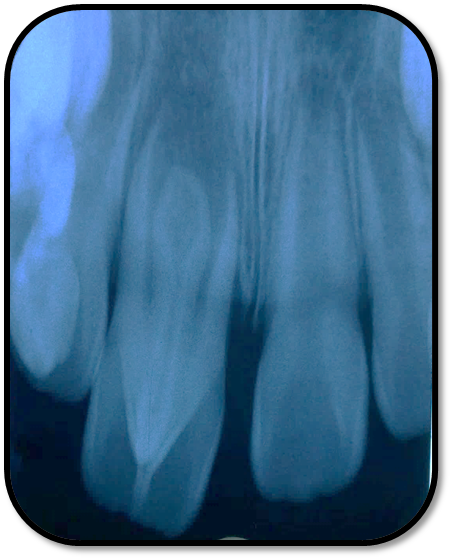

检查: 右上1牙冠略宽大,舌侧见粗大的畸形舌尖,叩痛(++),松Ⅰ°,唇侧牙龈红肿前庭沟膨隆扪痛,挤压唇侧龈缘溢脓,冷热测无反应,右侧上下1侧方颌,正中颌颌创伤。 X线:右上1发育7-8期,根管平行状,根尖孔宽大,约5-6mm宽,根尖周低密度影。髓腔根管宽大内见倒置牙影像,倒置牙可见髓腔。 余牙未见异常 6均已萌出建颌

随访复查: 治疗完成后1个月复查:右上1临床检查无阳性体征,叩痛(—),冷测无反应,无松动,牙龈无红肿,充填物完好,牙冠略有变色, X线检查:牙根根继续发育,可见钙化影像形成,如图示 治疗完成后7个月复查:临床检查无阳性体征,充填物完好,牙冠变色局部发黑,叩痛(—),冷测无反应,无松动,牙龈无红肿,临床及 X线检查:牙根继续发育,如图示 治疗完成后17个月复查:临床检查无阳性体征,充填物完好,牙冠变色局部发黑,叩痛(—),冷测无反应,无松动,牙龈无红肿。X线:牙根继续发育,根尖孔已近闭合。如图 讨论: 1、牙内陷(Dens invaginatus):是牙冠在生物学矿化开始前的内陷引起的一种罕见牙齿畸形。文献报道,牙内陷的发生率为0.04-10%不等,好发于上颌侧切牙。尖牙,双尖牙,磨牙,下颌侧切牙也有报道。 2、Oehlers将牙内陷畸形牙分为Ⅰ型和Ⅱ型均为釉质阻射层包绕的细沟状透射影,不同的是Ⅰ型局限于牙冠部分,不超过釉牙骨质界。Ⅱ型超过釉牙骨质界延伸至根管内,但不与牙周膜相通。Ⅲ型表现为囊袋状或细沟状透射影,由釉质阻射层包绕,由牙冠部延伸至根尖区,与牙周膜相通。其中type Ⅱ和type Ⅲ型根管系统极其复杂。内陷部位的釉质和牙本质可能有缺陷或缺失,很可能与牙齿髓腔有交通,这些特点使得该部位易龋坏且易进展影响牙髓 ,而且此类牙牙周组织不连续,易形成深牙周袋 ;畸形舌尖随牙齿萌出妨碍咬合,造成咬合创伤,尖细的畸形舌尖髓角长入,易于磨损或折断,极易发生牙髓炎症或者根尖炎症。由于根管系统复杂,所以治疗极其困难。 3、牙内陷的治疗: a、内陷处易患龋—尽早窝沟封闭或PRR,已龋坏者及时治疗,避免发展为牙髓炎根尖炎。 b、畸形舌尖不妨碍咬合较圆钝者可不做处理 c、干扰咬合和高而尖的舌尖可磨除畸形舌尖选择间接盖髓术、直接盖髓、部分冠髓切断。 d、牙髓已受累根据牙髓感染情况和牙根发育情况选择根管治疗、牙髓再血管化、MTA根尖封闭、根尖诱导成形。 e、内陷程度较重的Oehlers Ⅲ型患牙,因内陷结构与根尖区牙周膜相通, 其内容纳的细菌物质导致根尖周炎发生时, 通过常规根管治疗并不能使病变痊愈,还需根尖切除术加MTA倒充填。 f、拔除患牙。 4、内陷盲袋清理治疗时应注意:a、推荐手用根管锉,不推荐旋转镍钛,因为内陷盲袋内壁覆盖釉质,而非牙本质壁,且盲袋形状不规则,使用旋转镍钛器械容易折断。b、推荐使用超声根管预备(Bishop,2008)。c、推荐2.5%-5.25%次氯酸钠化学预备。